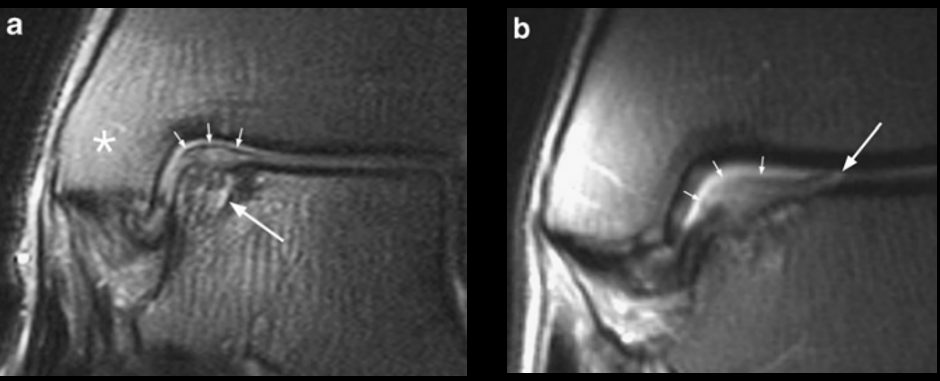

Рис. 8. МРТ: стадии 5а и 5б — субхондральная киста (хроническое повреждение)